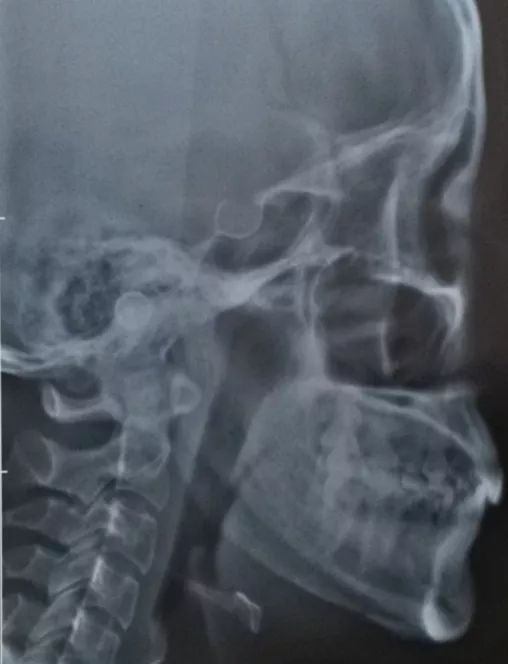

花了四万做了梦寐以求的下颌角整形。

因为遗传加上饮食习惯,我的下颌角极其肥大,侧面看整个是直角,并且外翻不对称。

图片来源:用户提供